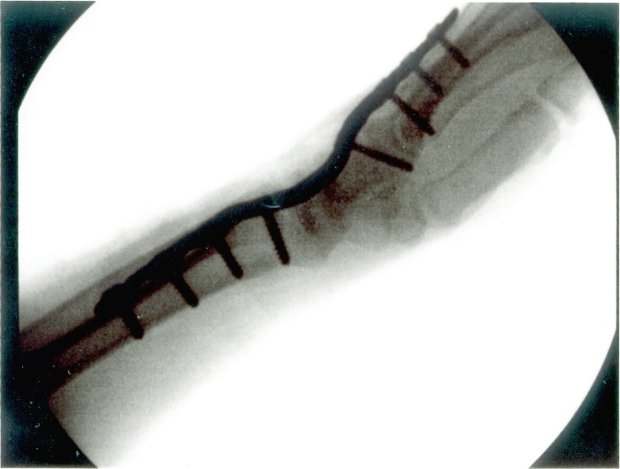

X-Ray with Plate 2 Days after Plate Removal 1 Day Later